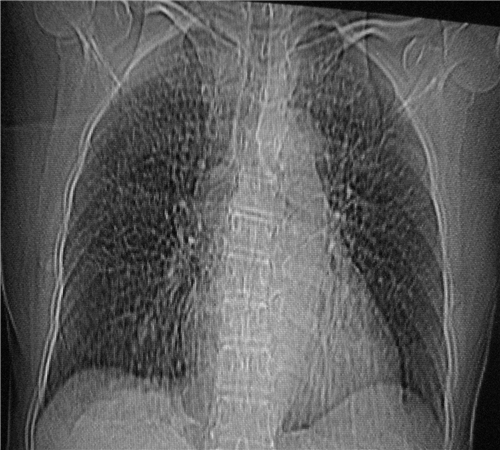

标题: CT26849:女67岁反复胸痛两天余,临床考虑夹层。 [打印本页]

标题: CT26849:女67岁反复胸痛两天余,临床考虑夹层。

右肺感染,未见夹层。

1)右肺感染性病变。2)建议行ct增强扫描或mri检查排除主动脉夹层。

双下肺感染,右侧显著。有无夹层,增强扫描后再诊断。

1.考虑双肺感染,右侧为重;2.建议ct增强或mri排除主动脉夹层